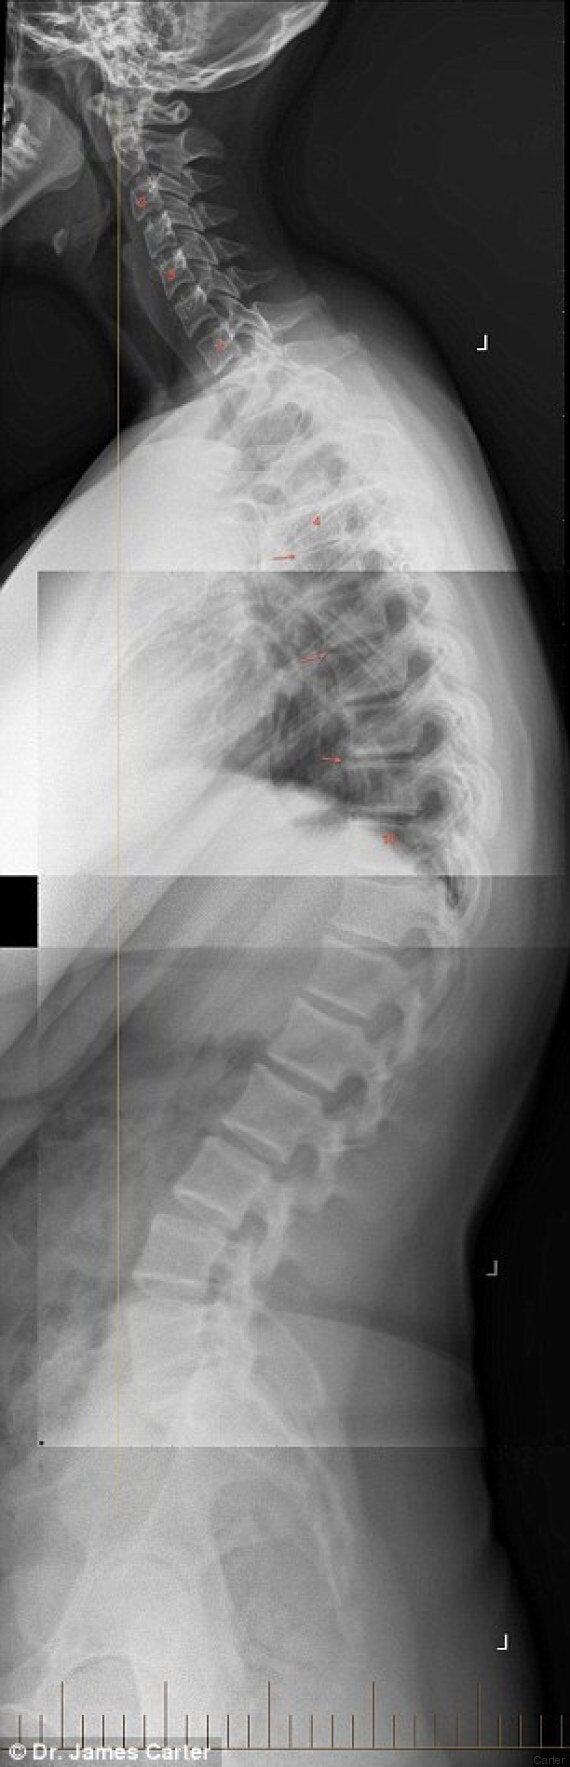

La Lastra Che Mostra I Danni Da Smartphone Alla Spina Dorsale Di Un Bambino Di Sette Anni Foto L Huffpost

La Lastra Shock Del Collo Di Un Bimbo Di 7 Anni Colpa Dello Smartphone